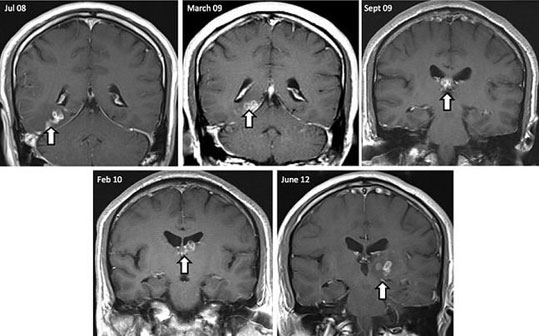

Μάλιστα το σκουλήκι, σύμφωνα με τους επιστήμονες, δεν έμενε ακίνητο στον εγκέφαλο, αλλά έκοβε βόλτες από το ένα ημισφαίριο στο άλλο, σε απόσταση τουλάχιστον πέντε εκατοστών, διασχίζοντας ευαίσθητα κέντρα του εγκεφάλου.